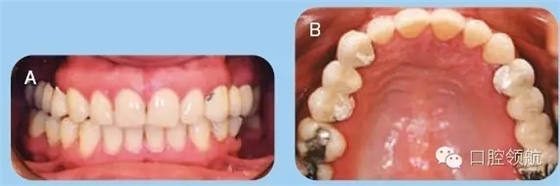

35歲白人女性患者,前來牙周科咨詢,要求修復兩側上頜象限的無牙頜區(qū)域。已存的固定橋修復失敗,患者要求行種植修復缺失牙。拆除患者已存的固定橋,重新預備基牙,并粘結臨時橋(圖1)。

圖1 (A)上頜以及下頜牙咬合關系的口內照。(B)上頜牙弓的牙合面觀。

● 兩側上頜1/4象限的缺牙區(qū)牙槽嵴在頰舌向以及垂直向形態(tài)欠佳(Seibert III類)(圖1)。